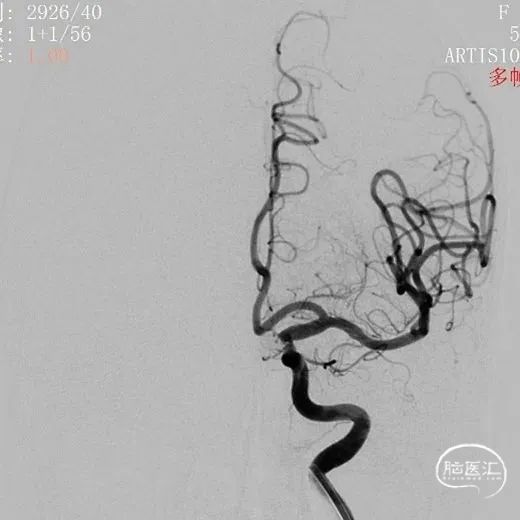

术前影像

术前影像

术前影像